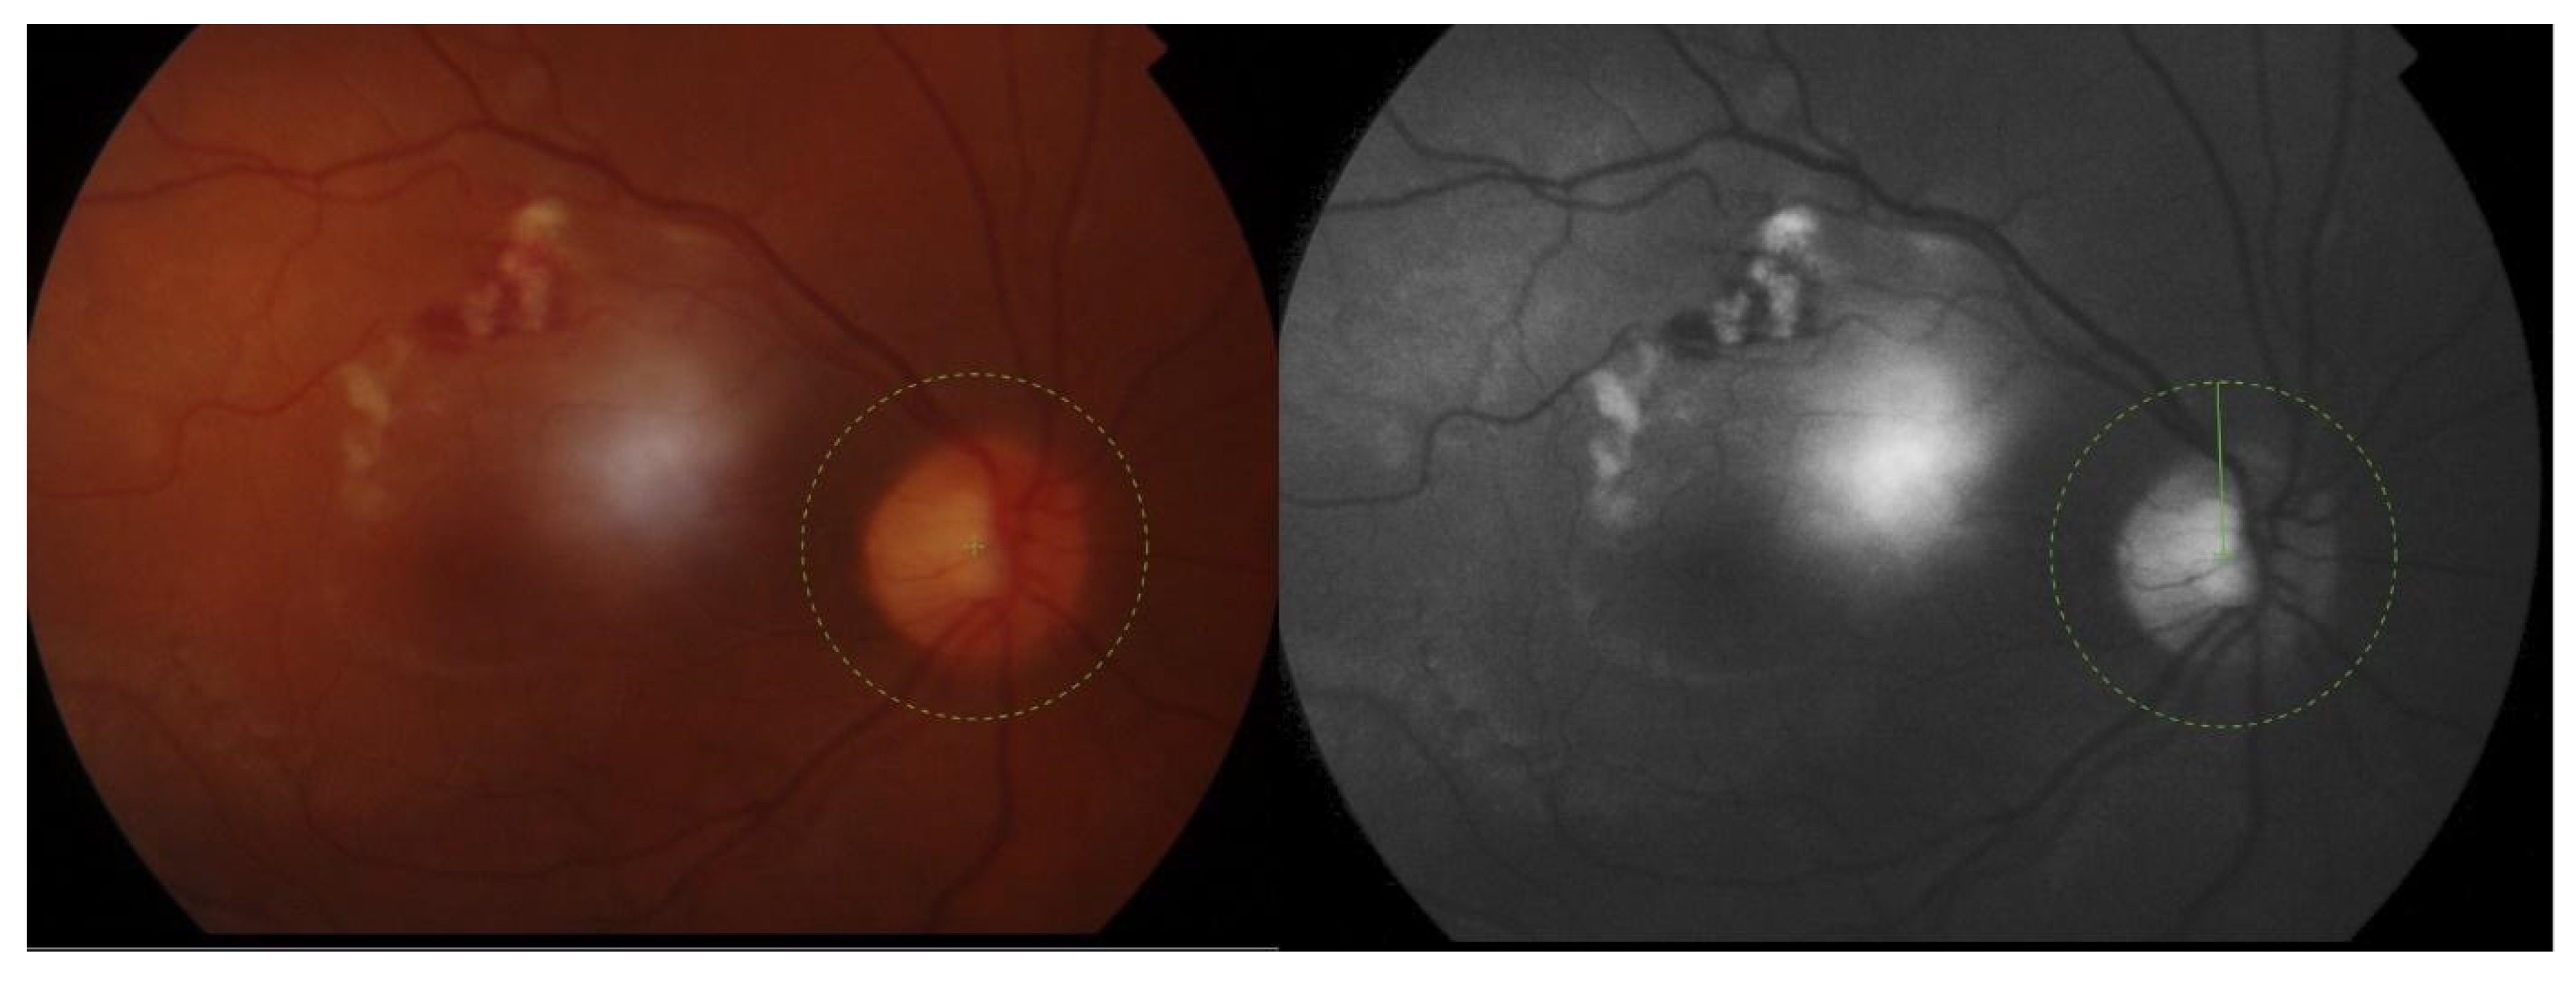

No photophobia or pain was reported.

Conjunctival redness was observed in the RE. A slit lamp examination revealed necrotizing anterior scleritis (Figure 2 and Figure 3) with the exposed choroid, covered with very thin or no sclera, chemosis, and the redness of adjacent conjunctiva from 8 to 12 o’clock. On the adjacent cornea, along 8-1 o’clock, a marginal ulcer was present (characteristic of GPA peripheral ulcerative keratitis) with no inflammation in the anterior chamber. In the posterior segment of the RE, the following signs of vasculitis were present along the upper temporal arcade: multiple cotton wool spots with flame hemorrhages, hemorrhages in the macular region, tortuous arteries, and dilated veins (Figure 4).

Figure 4. A photo of the fundus with vasculitis in the retinal vessels. Arteries and veins are involved. Cotton wool spots and hemorrhages are present. A color photo on the left and a red-free photo on the right.